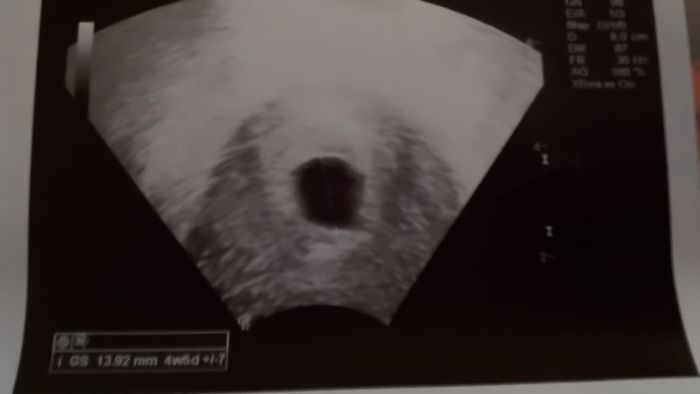

Tak co holky? Ja z te zpravy od doktora nic moc nevyctu a z fotky taky ne, jelikoz jsem tehotna poprve

Luciekro držím pěsti..taky mi přijde dost brzo,že uz te hned posílá na revizi..Jediný co s ty zprávy vyctu je ze plod není vidět..a deloha vypadá prázdná.Ale nejsme doktoři..měla jsi se zeptat.Hodně štěstí!